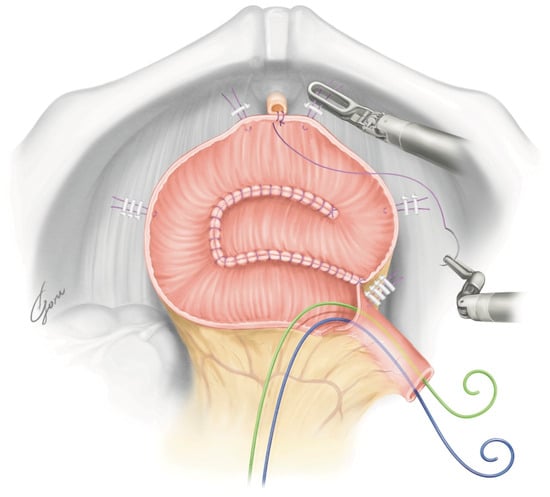

Figure 2.

The design of our posterior plate using the modified VIP method. Two supporting sutures were placed on the ileum near the urethra–ileal anastomosis.

The robot was redocked head-down at 10–12 degrees. The right supporting suture of the posterior plate was grasped with 4th arm forceps and the posterior plate was mobilized to the pelvic floor. A circumferential urethra–ileal anastomosis was performed using 3-0 VLoc sutures, similar to a robot-assisted radical prostatectomy (RARP) (Figure 3). The advantage of performing a circumferential anastomosis after creating a posterior plate is the visibility of the urethra during an anastomosis. If an opening is made and a urethral anastomosis is performed before detubularization, the part to be anastomosed may be difficult to visualize in Asian individuals with narrow pelvises. The anterior wall of the NB was continuously sutured so it was water-tight and tension-free using 3-0 VLoc sutures from the left and right toward the center. Via this manipulation, a folded structure could be obtained. A 20Fr Foley catheter was inserted and inflated with 20cc water when the anterior wall was half-closed. A bilateral 6Fr ureteral stent was passed through the anterior wall into the abdominal wall and inserted into each ureter using a guidewire. The remaining anterior wall was closured. Figure 4 shows the schema of the ileal NB created via our method.

In ICNB reconstruction, establishing UD after RARC is considered the most challenging step of the entire surgical procedure. Despite the increasing precedence of RARC, the majority of centers perform ECNB reconstruction because of the perceived difficulty of bowel reconfiguration and justified concerns regarding time efficiency compared with the open approach. Recently, the number of ICUDs performed has increased rapidly in NB reconstraction, along with the evolution of devices [11]. In Japan, the Studer or the modified Studer was often selected for open NB reconstruction. The Studer NB is still commonly the preferred technique despite a shift from ORC to RARC. Otaola-Arca et al. reported that Studer reconstruction was selected in 70% of ICNB surgeries [12]. In RARC, the NB reconstruction steps used in the open approach need to be modified. Proper intestinal positioning and manipulation are essential in ICNB reconstruction. The Ligaloop bands technique by Jonsson et al. is a popular choice [13]. An opening is created contralateral to the mesentery, and a urethra–ileal anastomosis is performed. Subsequently, a 60 mm stapler is inserted through the left port to transect the ileum and re-establish it with a side-to-side ileoileal anastomosis. Some surgeons use a suprapubic port to avoid excessive mobilization and bowel rotation against the stapler. Alternatively, after fixing the ileum to the pelvic floor, the intestine is separated, the transected bowel segment is detubularized, and a posterior plate is created. Thereafter, an opening is created and anastomosed with the urethra and posterior plate. Alternatively, a circumferential urethra–ileal anastomosis is performed without creating an opening. To extract the specimen, the Pfannenstiel incision is often carried out. The Karolinska-modified Studer, USC-modified Studer, Hautmann, Pyramid, Y-pouch, and VIP NB have been reported as typical ICNB reconstruction methods [14]. The Karolinska-modified Studer approach is the method most surgeons use to perform this procedure. It results in high daytime and nighttime continence rates [15,16]. The USC-modified Studer technique enables easy folding in robotic surgery via rotating the posterior plate 90 degrees counterclockwise [17]. However, in this technique, the posterior wall of the NB is pulled toward the urethra during a urethra–enteric anastomosis. Hence, when the anterior wall is laterally sutured, the NB could end up being vertically elongated. Subsequently, they updated the technique to include an additional fold to establish a more spherical shape [18]. In our modified VIP NB procedure, the shape of the posterior plate does not change significantly even when it is pulled toward the urethra (Figure 3). Our method achieves simple robotic manipulation without losing the folded structure. The advantages of an ICNB include a reliable urethra–enteric anastomosis, low insensible perspiration, and no need for excessive dissection of the ureter. These advantages also apply to the hybrid approach. If UD is performed extracorporeally, the ureteral length is typically longer than that achieved in intracorporeal UD, possibly contributing to a higher uretero-enteric stenosis rate [19]. The disadvantages include the extension of the operative time and head-down time. However, recent reports show that the total operative time is similar to that of ECNB reconstruction [11]. Although the use of an ICNB has been steadily increasing over time, it is associated with a five-times-higher risk of rehospitalization than an ECNB, which necessitates due circumspection [11]. Longer operative times and lower annual numbers of RARC procedures performed are risk factors for high-grade complications and readmission. ICNB reconstruction should be performed at a high-volume center.

Table 3 shows the reconstruction techniques for ICNB reconstruction and the hybrid approach [9,13,17,18,20,21,22,23,24,25,26,27,28,29,30,31,32,33,34,35,36]. We also demonstrate the direction in which the posterior plate is folded intracorporeally. The goal of NB reconstruction is to create a spherical, low-pressure reservoir with an appropriate intestinal length. A properly compliant NB prevents urinary incontinence. It also prevents ureter reflux and protects renal function. While there are various NB reconstruction methods, which method is used may not be functionally significant as long as the folded structure is firm. However, care should be taken in modifying the steps of NB reconstruction from ORC to RARC. In the past, longer detubularization tubes were utilized to create a large NB, but 40–45 cm detubularization tubes have recently become mainstream because NBs grow over time. In a surgical procedure that uses the afferent limb, the length of the afferent limb is often 10–15 cm. We used a 45 cm detubularization tube and a 10 cm afferent limb. In the urethra–enteric anastomosis part, an opening is often created at the antimesenteric site of the ileum before detubularization, and a urethral anastomosis is performed [13,20,21,22,23,24,26,27,31,32,35,36]. Alternatively, a circumferential urethra–ileal anastomosis is performed after detubularization [9,17,18], or an opening is created after detubularization, and a urethral anastomosis is performed [28,33]. In ORC, it is common to create a pouch and then perform urethral anastomosis, unlike in RARC. If the opening is made intracorporeally in the ileum before detubularization and the urethra is anastomosed and a pouch created, the urethra may be displaced and bent. A bent urethra prevents urination and prohibits urinary catheterization. Simone et al. performed NB reconstruction without detubularization of the NB neck to enable a physiological urethral anastomosis [34]. A circumferential urethra–ileal anastomosis is more natural because the NB neck is formed with the urethra as the fulcrum. To the best of our knowledge, an evaluation of varying urethral stricture rates and residual urine volumes due to differences in the urethral anastomosis has not been carried out. This is a topic for future studies. The direction in which the NB is folded is a challenging decision in robotic surgery. For the Studer NB, in open surgery, the NB is often folded from the bottom, which is the lowest point of the ileum mesentery, to the top or obliquely upward. In robotic surgery, some techniques fold the NB from top to bottom, and suturing must be performed at the lowest point of the mesentery. We improved the design of the posterior plate so that the NB can be folded from side to center. This procedure is preferable because the folding can be easily performed by robotic forceps and there is no tension when closing the NB anterior wall. We must be conscious of spherical NBs. In robotic NB reconstruction preceded by detubularization, a urethra–ileal anastomosis is often performed after posterior wall configuration. Therefore, it is necessary to consider the possibility that a large amount of tension is applied toward the foot during NB configuration under the Trendelenburg position, resulting in an NB shape that is different than expected. In our technique, the NB is created with this point in mind. We have a unique point of view that focuses on the fact that the shape of the NB changes when the surgical order for the NB configuration is changed, even if the ICNB reconstruction method is the same as that carried out in ORC. Many different NB shapes have been reported, and it is difficult to determine which method is better. It is important that the transition to robotic surgery does not compromise the quality of NB function. Ureteral anastomoses often use the Bricker or Wallace technique. Ureteral stents are inserted percutaneously or transurethrally. The Wallace technique requires guiding the left ureter to the right side in front of the sacral promontory. The Wallace technique is known to reduce the ureteral anastomosis stricture rate [37]. However, if the ureter is short, it may be better to anastomose the ureter directly into the NB.